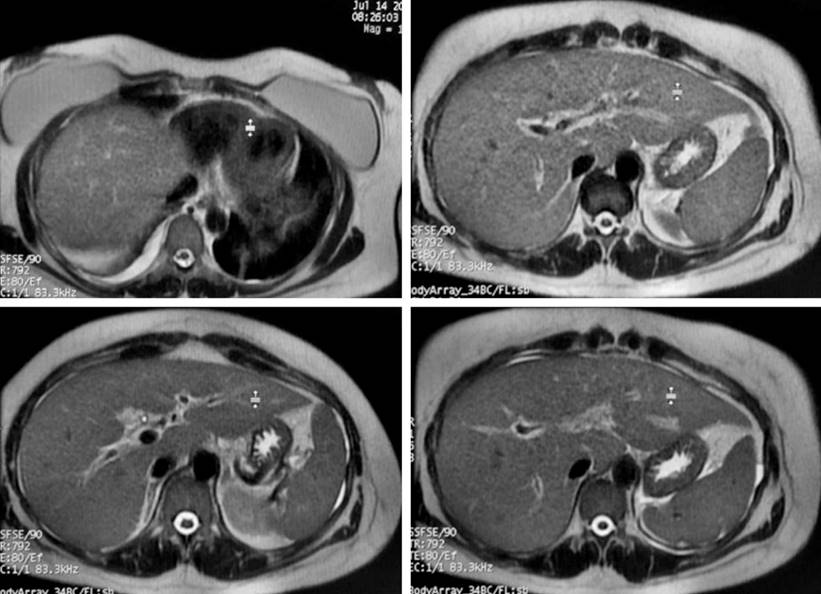

Figura 2 Colangiorresonancia de la paciente. Edema de las paredes de la vesícula y barro biliar en su interior sin observar cálculos en la luz vesicular ni en la vía biliar que originen obstrucción. Líquido libre en el espacio de Morrison y gotera parietocólica derecha. Líquido libre en la base pulmonar derecha. Hepatomegalia leve. Cortesía del departamento de radiología HUDN.